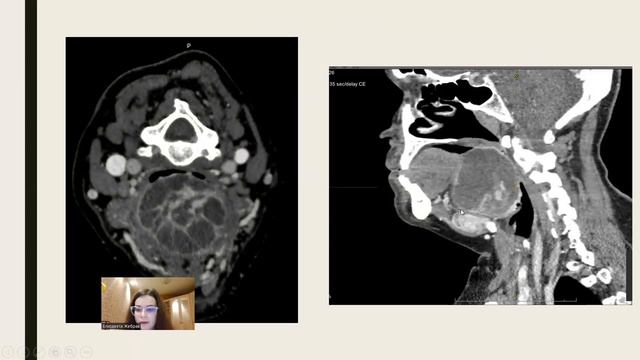

14. ЛЕЧЕБНО-ДИАГНОСТИЧЕСКИЙ АЛГОРИТМ ВЕДЕНИЯ ПАЦИЕНТА С ЭКТОПИЕЙ ЩИТОВИДНОЙ ЖЕЛЕЗЫ смотреть онлайн

06:27

14. ЛЕЧЕБНО-ДИАГНОСТИЧЕСКИЙ АЛГОРИТМ ВЕДЕНИЯ ПАЦИЕНТА С ЭКТОПИЕЙ ЩИТОВИДНОЙ ЖЕЛЕЗЫ

Worldwide Highlights 28 просмотров